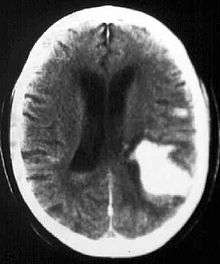

Intraparenchymal hemorrhage

Intraparenchymal hemorrhage (IPH) is one form of intracerebral bleeding in which there is bleeding within brain parenchyma. The other form is intraventricular hemorrhage (IVH).

Intraparenchymal hemorrhage accounts for approx. 8-13% of all strokes and results from a wide spectrum of disorders. It is more likely to result in death or major disability than ischemic stroke or subarachnoid hemorrhage, and therefore constitutes an immediate medical emergency. Intracerebral hemorrhages and accompanying edema may disrupt or compress adjacent brain tissue, leading to neurological dysfunction. Substantial displacement of brain parenchyma may cause elevation of intracranial pressure (ICP) and potentially fatal herniation syndromes.

Computed tomography (CT scan): A CT scan may be normal if it is done soon after the onset of symptoms. A CT scan is the best test to look for bleeding in or around your brain. In some hospitals, a perfusion CT scan may be done to see where the blood is flowing and not flowing in your brain.